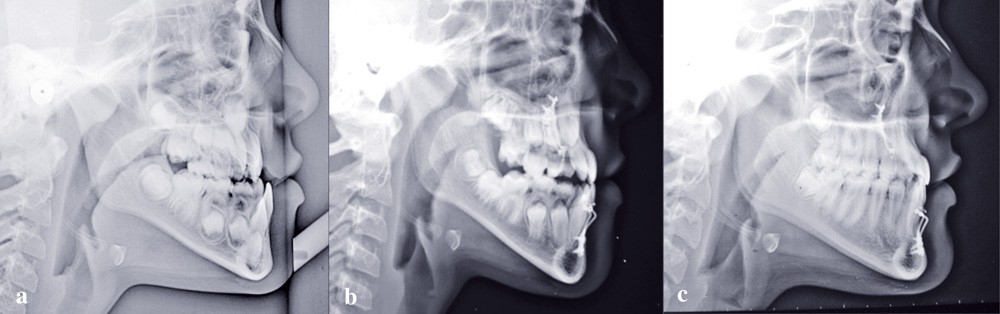

Les téléradiographies de profil confirment la croissance du maxillaire avec une légère tendance rotationnelle antérieure et une avancée du point A de 8 mm. La croissance mandibulaire est homothétique sauf dans la région du point B où elle est freinée (fig. 6-7).